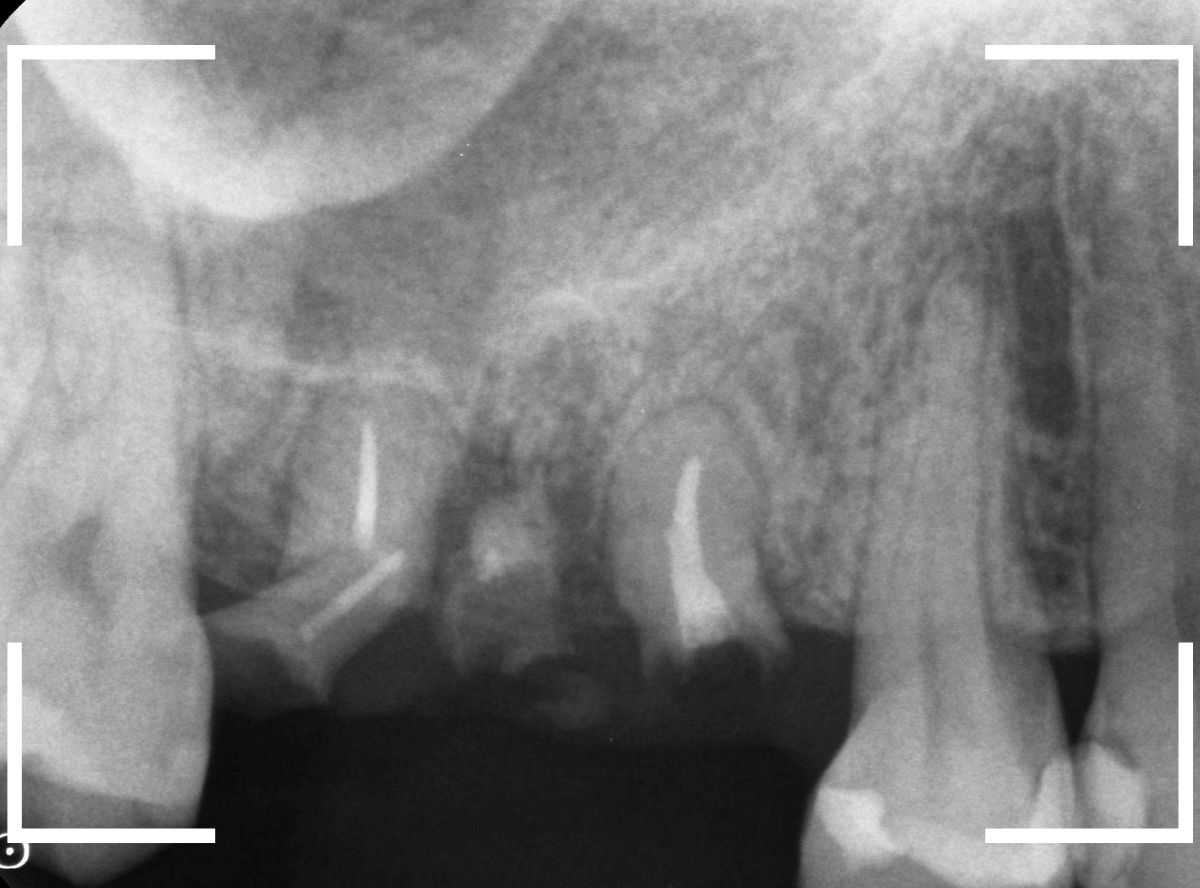

Case.1 残根状態の歯

虫歯を放置してしまい、ボロボロになってしまった歯の抜歯ケースです。

歯肉の中まで虫歯が広がってしまうと、多くの場合、抜歯をしなくてはいけません。

その上、抜歯も苦労するケースになってしまいます。

※出血多く、閲覧注意です!

レントゲン写真でも、ほとんど残ってる歯が確認できません(残根状態(歯の根っこだけ残っている状態)といいます)。

これでは、抜くのも大変そうです(><)

歯肉をかきわけながら、何とか全て抜歯しました。

歯は細かく砕けてしまい、大変な抜歯になりました。

このような状態になる前に、歯科受診するようにおすすめします。